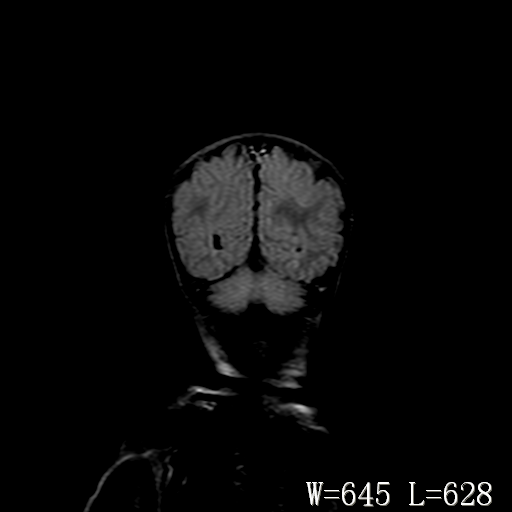

男,4天,发复抽搐1天。

新生儿正常颅脑

hie?

脑干形态欠规则,信号增高,不知怎么解释?

脑干背侧面t1高信号是,新生儿正常已经髓鞘化好的部位